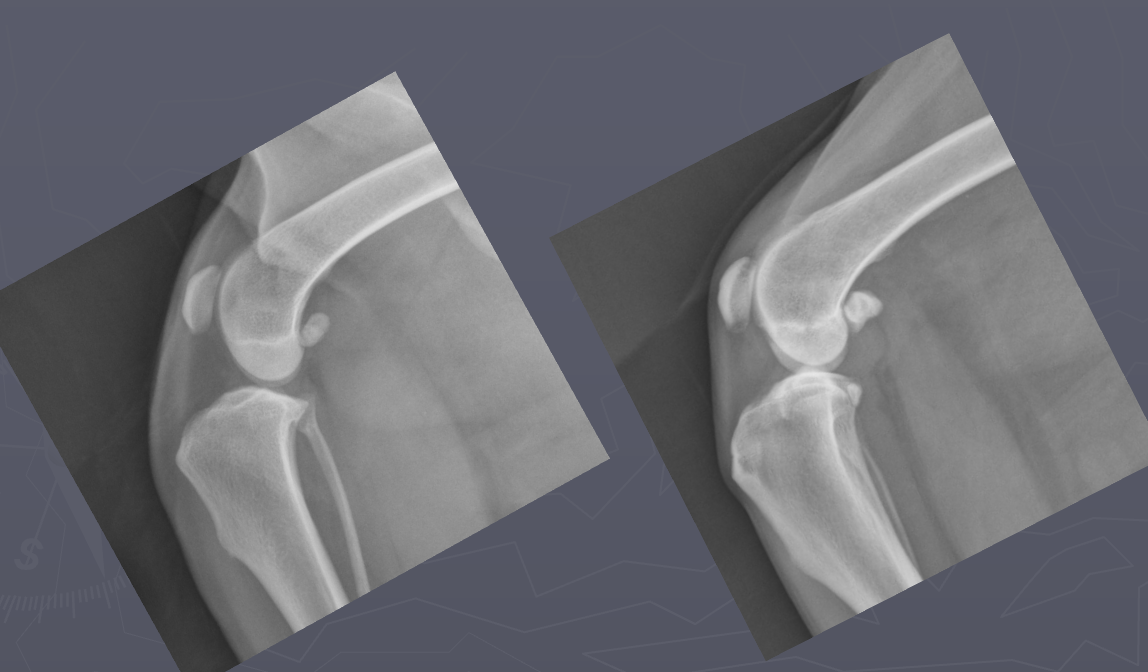

Which radiograph is normal and which is abnormal? Why?

Left: normal; infrapatellar fat pad is of normal size and placement

Right: abnormal; infrapatellar fat pad is displaced and compressed due to intracapsular swelling

Left: normal; deep fat caudal to the joint is in normal position

Right: abnormal; displacement of fascial planes caudal to joint due to intracapsular swelling; joint pouch buldges